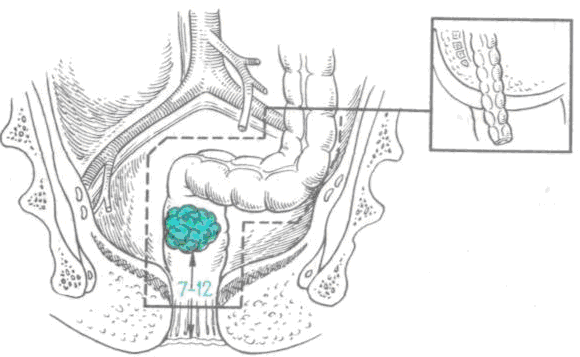

Диагностика непроходимости кишечника у собак

При подозрении на кишечную непроходимость после врачебного осмотра необходимо сделать рентгеновские снимки брюшной полости, желательно — в двух проекциях, т.е. снимок в положении на боку и в положении на спине. Поскольку на рентгеновских снимках мы видим двумерную картинку — тень от объемного (трехмерного) тела животного, то контуры разных органов накладываются друг на друга, и только сделав снимки в двух проекциях, бывает возможно понять, где локализуются те или иные структуры, видимые на снимке. На этих снимках можно увидеть рентгеноконтрастные вещества, плотность которых значительно превышает плотность мягких тканей организма и рентгенопрозрачные очаги, как правило — очаги газообразования, плотность которых наоборот, значительно ниже плотности мягких тканей.

Шарики от детского магнитного конструктора «Неокуб» в желудке у мопса.

Кроме того, на рентгеновских снимках можно увидеть признаки перитонита — воспаления серозных оболочек брюшной полости с выпотом жидкости. Такая находка в сочетании с признаками кишечной непроходимости, как правило, говорит о возможном прободении кишечника и о необходимости срочной операции.

Обнаружение контрастных инородных предметов, как правило, позволяет быстро и однозначно поставить диагноз и предложить владельцам животного начать готовить питомца к операции.

Значительные очаги газообразования в кишечнике могут быть косвенными признаками кишечной непроходимости. Однако, косвенные признаки требуют верификации (подтверждения) диагноза. Поскольку речь идет о необходимости хирургической операции, и врач и владелец всегда хотят максимальной определенности.